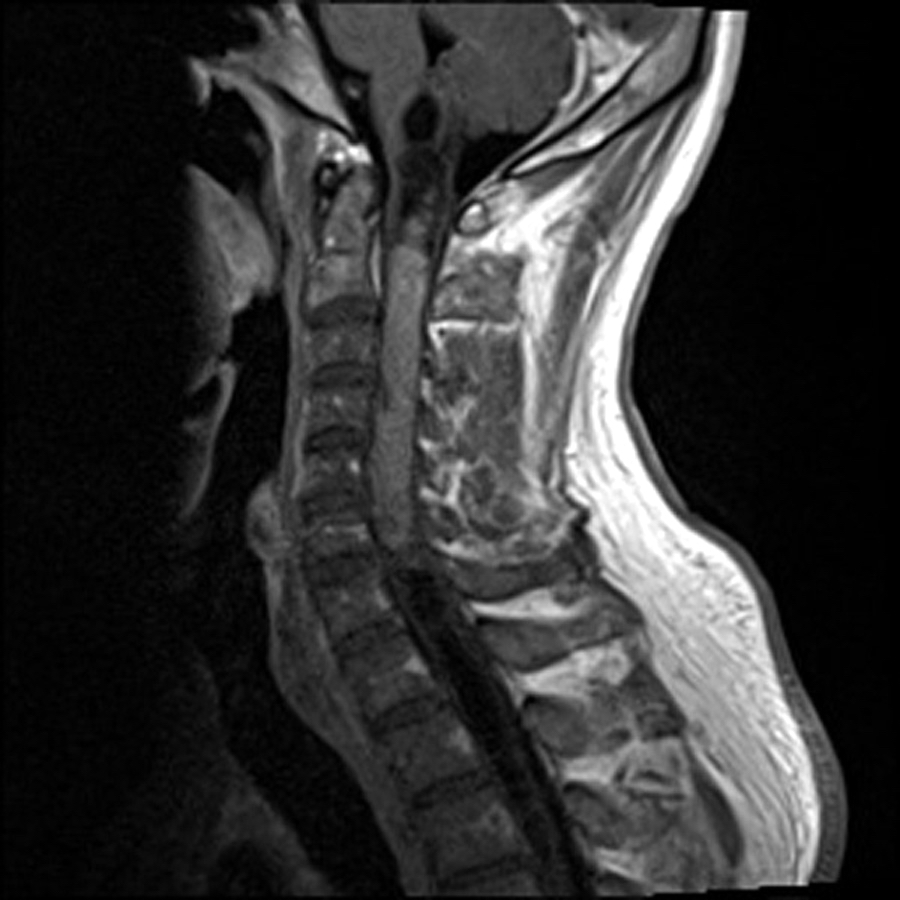

Radiology description

- Commonly discrete, well circumscribed mass with avid uniform contrast enhancement

- Hyperdense on computed tomography and T2 hyperintense on magnetic resonance imaging

- Reference: Childs Nerv Syst 2009;25:1203

Radiology images